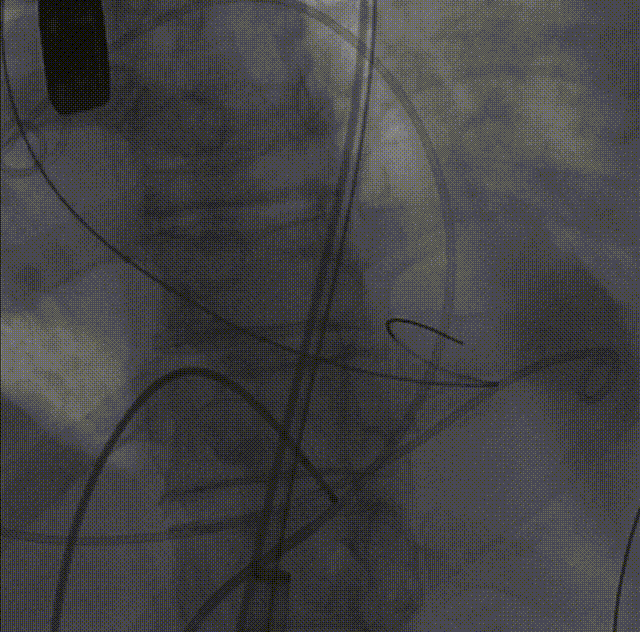

26VenusAplus+snare

瓣膜内22mm球囊后扩张,左冠无显影